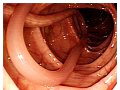

หมออัพคลิปนำพยาธิตัวยาวออกจากปากคนไข้

แพทย์วิสัญญีชาวอเมริกัน "ไมโร ฟูกูระ" ผู้มีผู้ติดตามมากกว่าล้านคน ได้โพสต์คลิปที่แสดงให้เห็นว่า "ทีมแพทย์คนหนึ่ง กำลังดึงพยาธิตัวตืด ที่ยาวมากๆ ออกจากปากของผู้หญิงคนหนึ่ง นอนตะแคงบนเตียงในโรงพยาบาล พร้อมกับใส่ชุดป้องกันไว้ที่ปาก ซึ่งหมายความว่าเธอกำลังเข้ารับการตรวจด้วยกล้อง ซึ่งทำให้ชาวเน็ตจำนวนมากตกใจกันหนักมาก!! โดย "ไมโร ฟูกูระ" ใช้โอกาสนี้เตือนประชาชนว่า "การกินเนื้อหมูดิบหรือปรุงไม่สุก อาจท.. ดูเพิ่ม